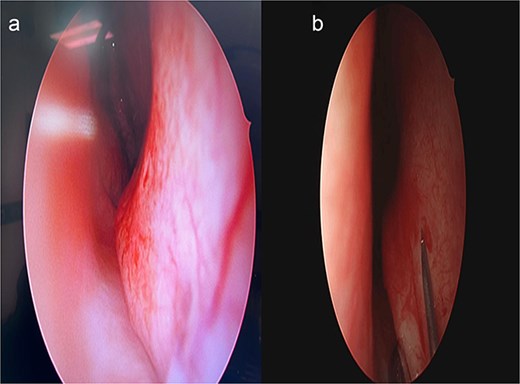

The surgical approach begins with endoscopic visualization of the deviated segment (Fig. 2).

Intraoperative endoscopic view of the deviated nasal septum prior to correction.